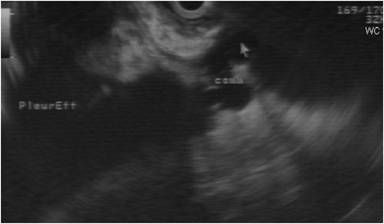

A seventy-nine-year old man, known alcoholic who presented with complaints of cough, right sided chest pain and abdominal pain since 3 months. There was right sided massive pleural effusion. Pleural fluid analysis showed mildly elevated amylase levels of 1,725 U/L. CT showed cystic fluid collection arising from the body of pancreas and communicating with the pancreatic duct with the collection tracking superiorly around the gastroesophageal junction into the posterior mediastinum where small multicystic collections were noted communicating with the right pleural effusion. ERCP was not attempted as CT had demonstrated wide communication of the duct with pseudocyst, significant atrophy of the pancreatic parenchyma distal to the ductal disruption and an impacted calculus proximally, hence chances of technically successful endoscopic stenting were deemed low. Since the pancreatic pseudocyst was behind the stomach endoscopic ultrasound guided transmural drainage of pseudocyst was attempted. Endoscopic ultrasound demonstrated a small well defined pseudocyst in the lesser sac with communication with the main pancreatic duct and pancreatico-pleural fistula with pseudocyst communicating with right pleural effusion (Figure 6).Endoscopic transmural gastric drainage of pseudocyst was done and the tapped fluid showed grossly elevated amylase levels of 109,800 U/L. However due to small size of the pseudocyst and immature walls, dislodgement of the catheter was noted on follow up CT. The dislodged catheter was snared endoscopically. The patient was nonresponsive to conservative management and had persisting pleural effusion and abdominal pain. He underwent successful surgical treatment which included distal pancreatectomy, splenectomy and proximal pancreatico-jejunostomy. Intraop complication included bleeding from short gastric vessels and splenic vein and brief episode of hypotension requiring dopamine infusion. Postoperatively the patient required ventilator support for one day. The patient also required drainage of the right pleural fluid collection postoperatively. The total hospital stay was of 26 days. Long term follow up had not shown any recurrent symptoms (Table 1).

Figure 6. Endoscopic ultrasound image acquired superiorly shows communication (comm.) of cyst (arrow) with pleural effusion. |